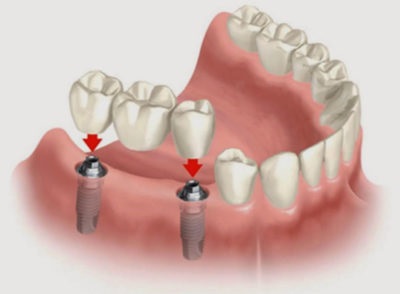

Ideiglenes protézis előnyösen, ha Beragasztó nem lehetséges, bármilyen okból. Sokszor előfordulhat, hogy várni a gyártás állandó protézisek - eltávolítható vagy nem eltávolítható, mint ez a folyamat eltarthat több mint egy hétig. Ugyanez vonatkozik a fogászati implantátumok egyik szakaszában visel gyógyító ütköző, időrendben között helyezkedik el a gépet a implantátum és a felépítmény telepítést. Még kedvező gyógyulási szövet alakítója alkalmazás ideje legalább 7-10 nap, melynek során űrt tátongó mosoly vonal ajánlott álcázás. Ez fontos gyakorlati szempontból: egy ideiglenes protézis, hogy megvédje a gingivális rész, alatt készült állandó protézis, a felesleges sérülést és invázióját patogén mikroorganizmusok.

Egy vagy két hiányzó fogak könnyen cserélhető azonnali fogpótlás, akinek a neve utal az értelemben a közvetlenség, sürgős. Egy ilyen eszköz, az úgynevezett „pillangó”, annak megjelenése során rögzített, egy látogatás a fogorvos, és nem igényel előzetes felkészülés fogak. Rögzítés végezzük Clipper - horgas folyamatok, kapaszkodva a koronát a szomszédos fogak.